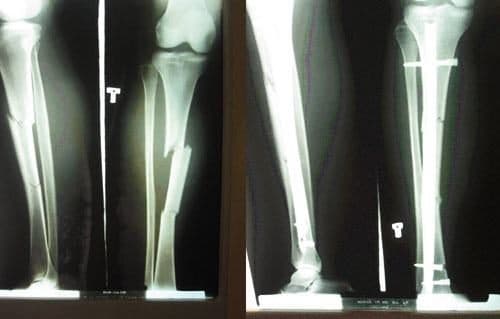

Xương chày nằm ở đâu? Gãy xương chày có nguy hiểm không?

Xương chày nằm ở phía trước trong của căng chân và là xương có kích thước lớn nhất trong toàn bộ chi dưới. Vậy xương chày là xương gì, có cấu tạo, chức năng thế nào? Mời bạn đọc cùng theo dõi bài viết dưới đây. 1. Xương chày là xương gì? Xương chày hay […]